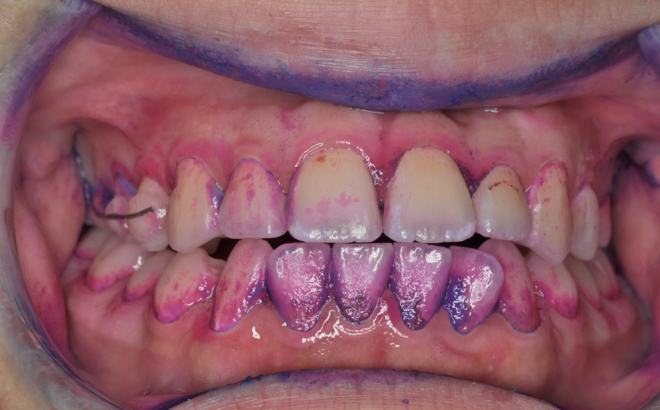

不正咬合のある人は歯ブラシがしにくく、まして矯正装置を付けるとむし歯や歯周病のリスクが大きくなります。そこで当院では矯正治療中の患者さん全てにツートーン(病原性の強いプラークが青く、そうでないプラークは赤く染まる染め出し液)での染め出しとブラッシング指導、PTC(プロフェッショナルトゥースクリーニング)を行っています。